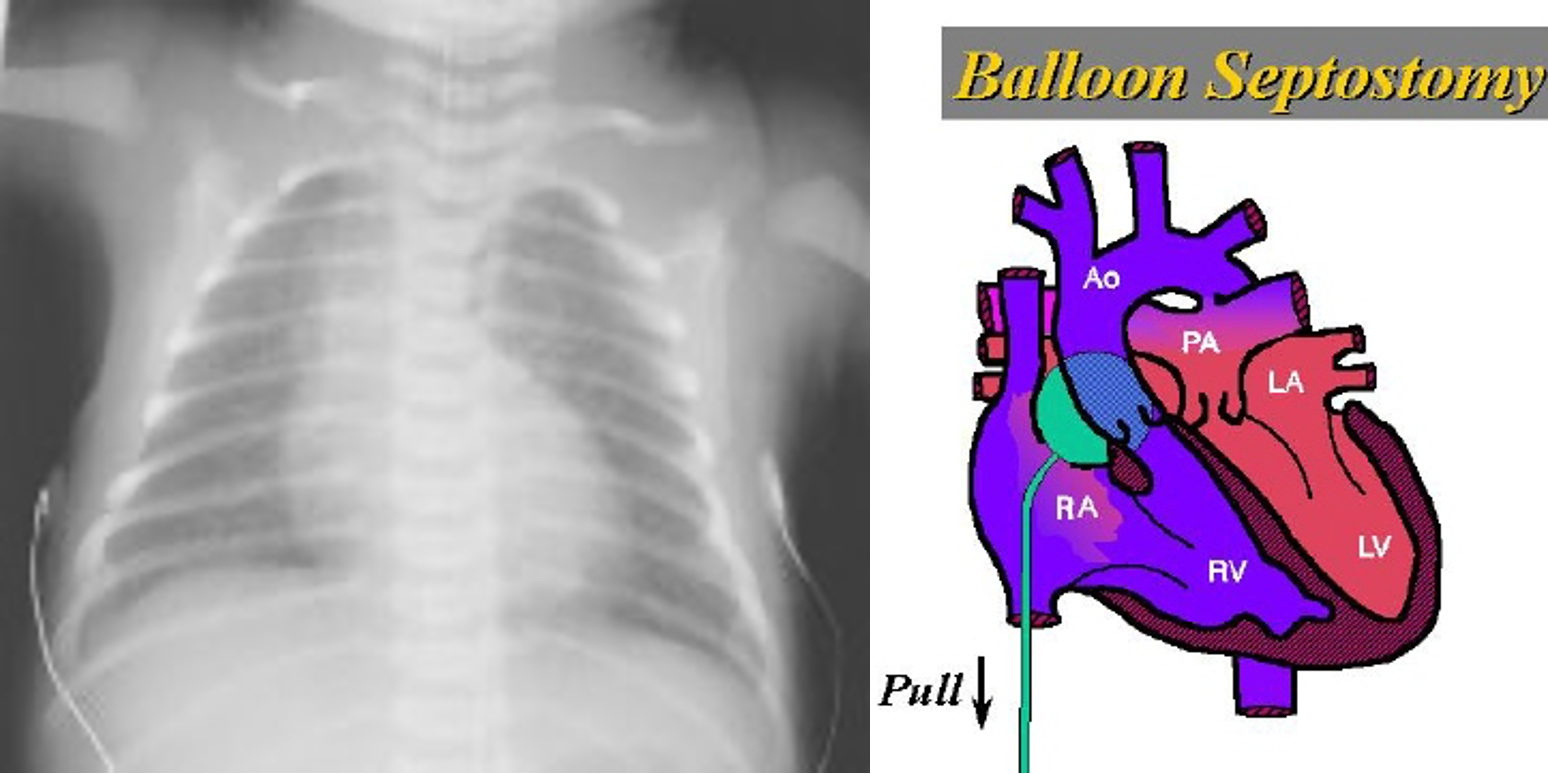

X-ray

- Generalized cardiomegaly

- Narrow mediastinum

- Increased PVM

- May be normal